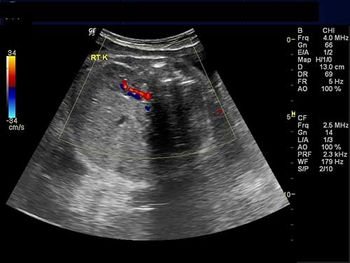

This 18-week fetus has a vascular anomaly. Can you identify it?